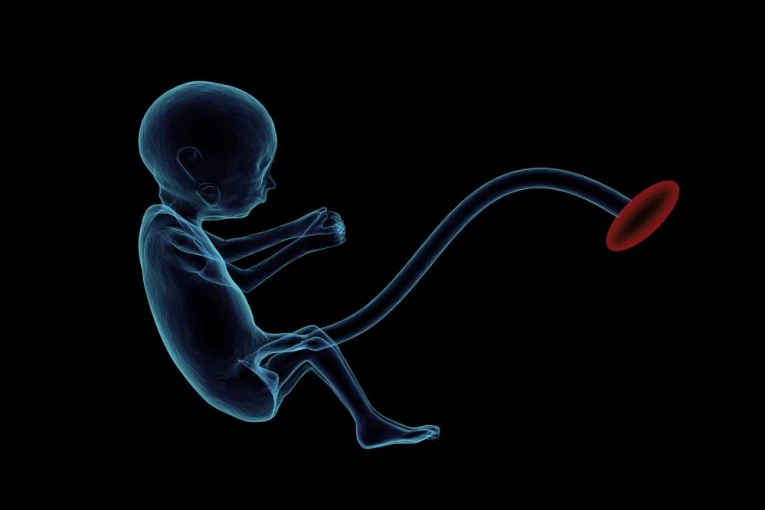

Direktor Regenerativnog medicinskog centra iz Barselone i doktor Angel Raja objašnjava da se eksperimenti sa himerama suočavaju sa etničkim barijerama.

- Šta se dešava ukoliko ljudska matična ćelija pobegne i formira ljudski neuron u mozgu životinje. Da li će biti posledica i šta se dešava ukoliko se ove matične ćelije preobrate u ćelije sperme - zapitao se on.

Nunjez kaže da istraživanje tima ima mehanizme da se samounište ljudske ćelije koje "migriraju" u mozak.

Kako bi se izbegli etički problemi, naučna zajednica je odredila 14 dana kao crvenu liniju za trudnoću, što opet nije dovoljno za razvoj ljudskog centralnog nervnog sistema.

Nunjez kaže da su svi embrioni himere uništeni pre isteka vremena, kao i da nijedan nije iznesen do kraja.

U Španiji, ova vrsta istraživanja je uglavnom zabranjena i organičena za istraživanje smrtonosnih bolesti, a Nunjez objašnjava da se eksperimenti ovog tipa rade u Kini jer se ne mogu raditi u Španiji.

- Krajnji cilj je da se napravi ljudski organ koji može da se presadi - rekla je ona za El pais.